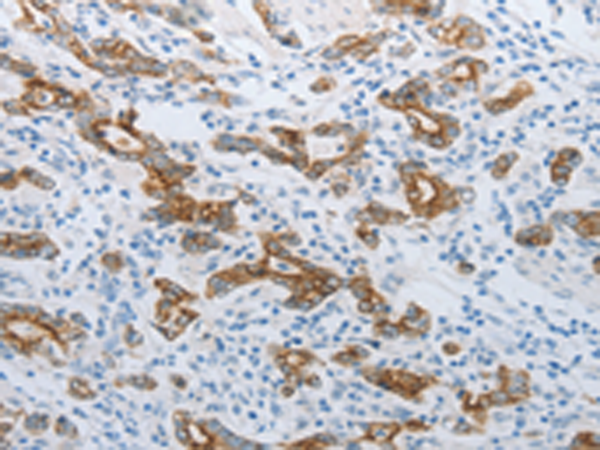

分类: 科研抗体货号: P04384别名: NIS; TDH1应用: WB,IHC反应种属: Human